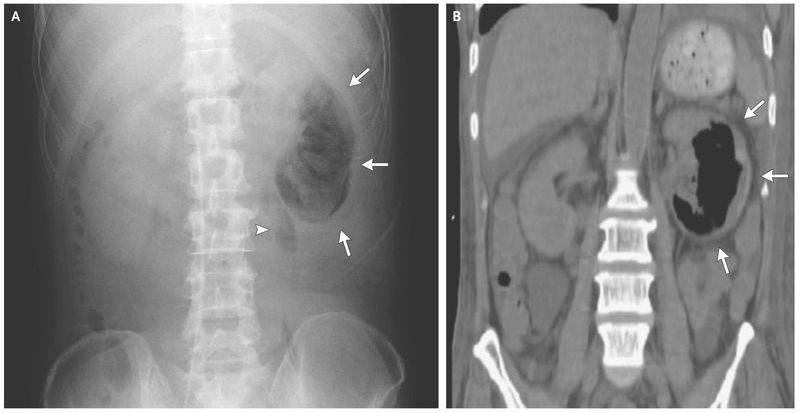

A 51-year-old man presented with fever and general malaise of 2 weeks’ duration. He had had diabetes mellitus for the preceding 20 years, and at the time of presentation this condition was poorly controlled. On admission to the hospital, his white-cell count was 10,800 per cubic millimeter (normal range, 3900 to 9800). The C-reactive protein level was 8.6 mg per deciliter, blood urea nitrogen 90 mg per deciliter (32 mmol per liter), creatinine 4.9 mg per deciliter (430 μmol per liter), and glycated hemoglobin 11.2%. Abdominal radiography (Panel A) and computed tomography (Panel B) revealed gas collection in the parenchyma (arrows) and perinephric space (arrowhead) of the left kidney. The patient received a diagnosis of emphysematous pyelonephritis, possibly caused by retrograde infection related to diabetes-associated neurogenic bladder. Escherichia coli was isolated in blood culture but not in urine cultures. The patient was treated with antibiotics; the infection resolved, and renal function improved (the blood urea nitrogen level declined to 23 mg per deciliter [8 mmol per liter] and creatinine to 2.6 ml per deciliter [230 μmol per liter]).